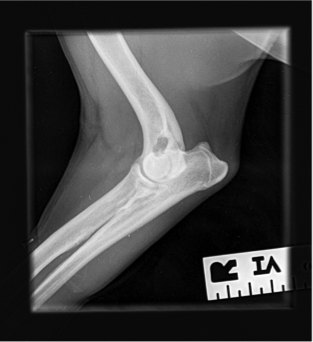

- With deterioration and lack of resolution of Charlie’s discomfort he was referred to Weighbridge Referral Centre for radiographs and evaluation of his right forelimb and cervical spine. A small osteophyte was found along the caudal border of the humeral head and there was evidence of remodeling of the medial coronoid process which could be indicative of a degree of elbow dysplasia; however, these findings did not necessarily explain the degree of pain that Charlie has been experiencing clinically. The owner reported that this week prior to our evaluation had been particularly painful for Charlie. He is currently on Metacam, but the owner does not believe that it is helping as much as it did when Charlie was initially placed on the medication.

- Radiographs: